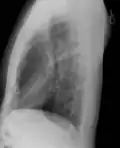

Рентгенография грудной клетки

Рентгенограмма грудной клетки в прямой проекции, норма.

Рентгеногра́фия органов грудной клетки — классическое проекционное рентгенографическое исследование грудной клетки, применяемое для диагностики патологических изменений грудной клетки, органов грудной полости и близлежащих анатомических структур. Рентгенография грудной клетки является одним из наиболее распространённых рентгенографических исследований.